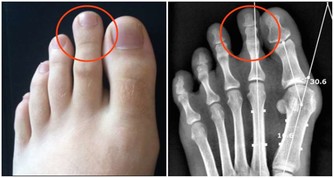

示意圖via